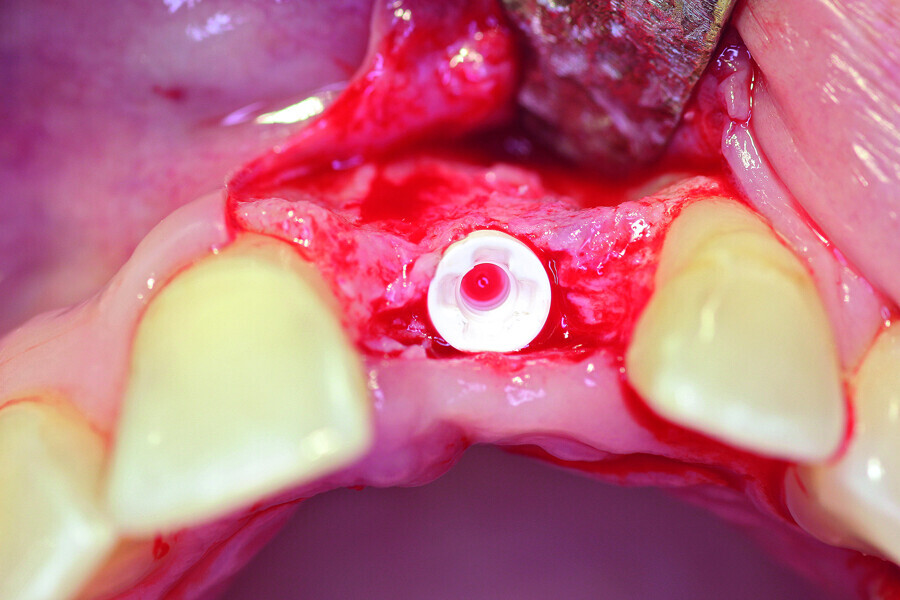

Fig. 5a: A two-piece ceramic implant was inserted.

Fig. 5b: A two-piece ceramic implant was inserted.